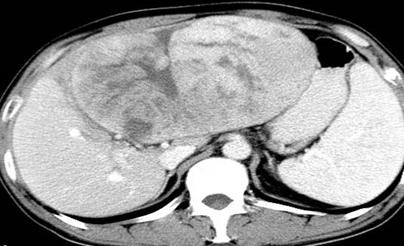

肝血管瘤:大多数为肝海绵状血管瘤,大者可达10cm以上,是最常见的肝脏良性占位,女性发病率多于男性,在CT和核磁有特征性表现,特别是核磁,呈圆形或类圆形低信号,在T2相病灶呈高信号,又称“灯泡”征;

图中白色为血管瘤